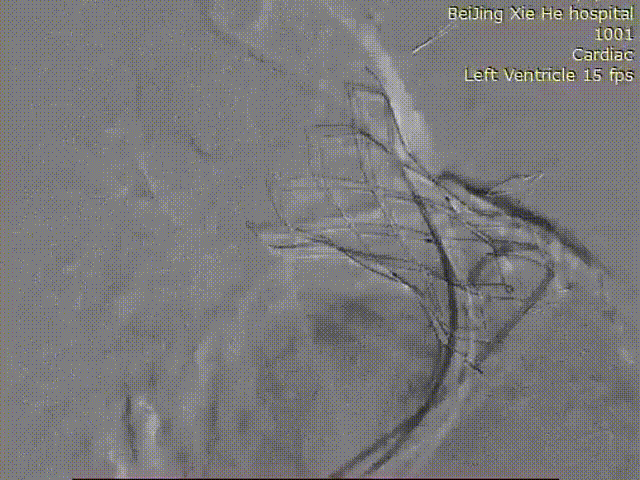

术前基于增强CT图像对肺动脉瓣、肺动脉和右心室空间结构进行三维建模和精准测量

超声显示经导管肺动脉瓣置换术后肺动脉瓣反流消失